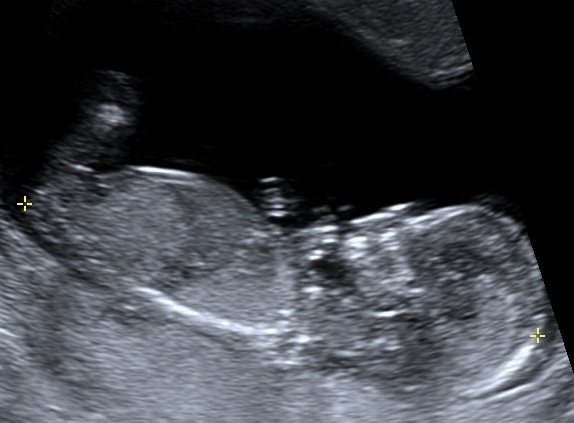

Attachment 19527Attachment 19528At my NT scan at 13 weeks (baby measured 14 weeks 1 day) the tech said if she had to bet she would say it is a girl. Yesterday I had a scan at 16 weeks(not sure where baby is measuring) with my ob he said he's not an expert but that he agrees with the tech that baby is a girl and that we can tell family just not announce on facebook(not a problem for me :) ). I'm still nervous that our little girl is actually a boy that's why I would love some more opinions/guesses from you all. Thanks!